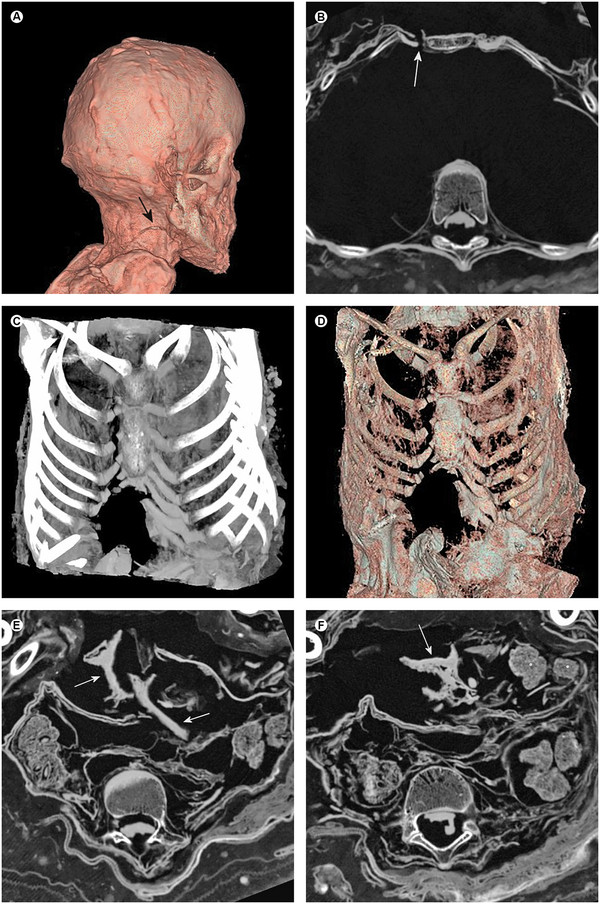

1480–1650 гг. н. э.).Снаружи мумия, размер которой 71×50 см, напоминает стилизованную куклу в наряде инков: маленькая головка украшена орнаментальной повязкой, которая поддерживает парик из человеческих волос, заплетенных в две косички. На лице выделен только нос. Одежда «куклы» — широкая клетчатая туника — напоминает токапу, традиционное одеяние инков, состоящее из разноцветных тканевых кусочков. На шее «куклы» висит ожерелье с ракушкой двустворчатого моллюска шарнира и четыре маленьких мешочка, в которых, вероятно, находились благовония и зерна кукурузы. Тунику и шею опоясывают пращи — оружия для метания камней или небольших металлических шариков. За пояс заткнуты три мешочка, сшитые из меха с ног ламы. Две обувные подошвы и ремешки, найденные между слоями материи, — это, по-видимому, сандалии.

Тело не было специально мумифицировано: внутренние органы оставлены на месте, нет следов обработки бальзамическим составом. Вероятно, мумификация произошла просто за счет высыхания в жарком сухом климате. Тем не менее почти все внутренние органы, мягкие ткани головы и опорно-двигательной системы хорошо сохранились. Их изучение показало, что при жизни ребенок сильно болел: нейрофриброматоз I типа, болезнь Шагаса, и, вероятно, туберкулез. Эти болезни в Империи инков были в то время широко распространены, из-за чего половина детей не доживала до 15 лет. Кроме того, скудное количество подкожного жира указывает на довольно высокую степень истощения.

Однако смерть ребенка, скорее всего, была вызвана не болезнями. Томографическое обследование показало множественные насильственные повреждение скелета и мягких тканей: перелом шейных позвонков, большеберцовой и левой плечевой кости, разрез на груди, смещение печени за пределы брюшной полости, смещение некоторых зубов. Откуда появились такие серьезные травмы? Образовались ли они уже после смерти мальчика, было ли это убийство, следствие катастрофы или обряда жертвоприношения — неизвестно.